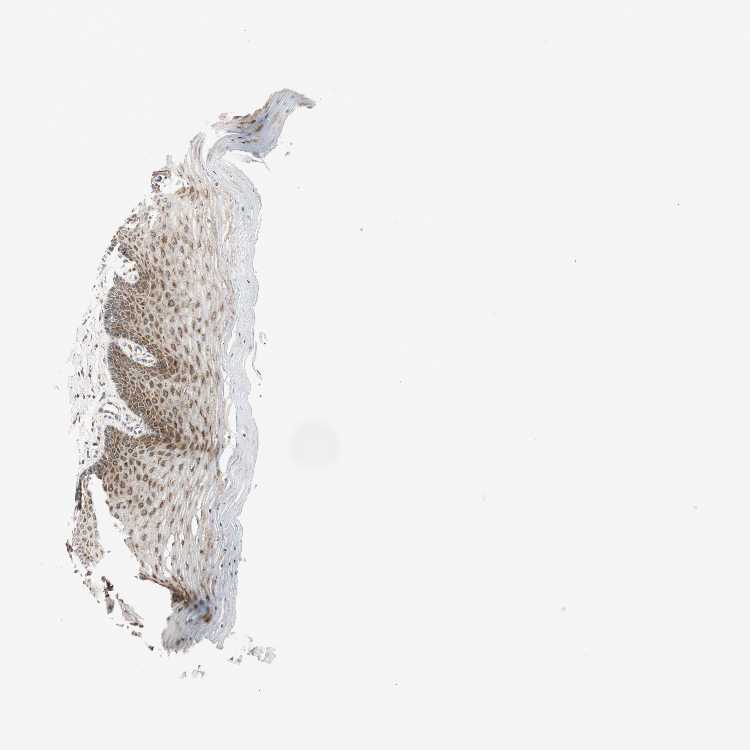

CERVIX - Antibody stainingi

Antibody staining in the annotated cell types in the current human tissue is reported as not detected, low, medium, or high, based on conventional immunohistochemistry profiling in selected tissues. This score is based on the combination of the staining intensity and fraction of stained cells.

Each image is clickable and will lead to virtual microscopy that enables deeper exploration of all samples and also displays staining intensity scores, fraction scores and subcellular localization as well as patient and tissue information for each sample.

Antibody CAB008375

Glandular cells High

Squamous epithelial cells High